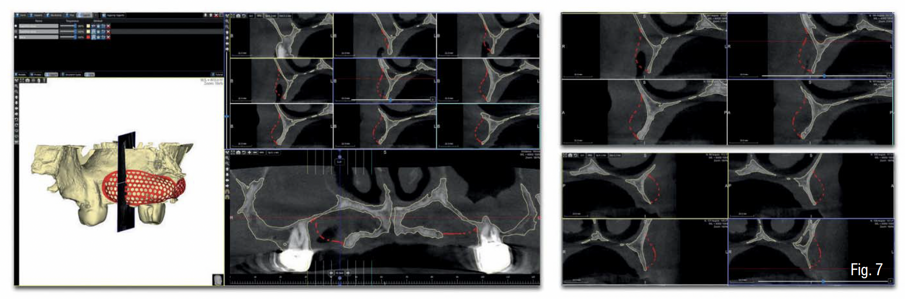

In accordo con il paziente si decide di eseguire un intervento di rigenerazione ossea guidata (GBR) mediante una griglia in titanio customizzata e membrane riassorbibili (Figg. 2-4). Pertanto, 1 mese prima della chirurgia, è stato creato un modello osseo virtuale in formato .stl del mascellare sup. tramite segmentazione, a partire dai file .dicom della CBCT, utilizzando un software biomedicale dedicato (BTK- 3D, Biotec Srl, Dueville, Vicenza, Italy); è stato quindi eseguita la progettazione virtuale dell’aumento di volume osseo necessario per inserire gli impianti e la successiva progettazione della griglia customizzata al di sopra del volume aumentato; infine, è stata realizzata la griglia in titanio vera e propria mediante tecnologia di stampa 3D basata su sinterizzazione laser del titanio (3D-Mesh BTK, Biotec Srl, Dueville, Vicenza, Italy) (Figg. 5-8).

Infine, è stata eseguita un’attenta chiusura di prima intenzione dei lembi chirurgici, mediante una sutura a doppio strato, costituita da una linea di punti a materassaio orizzontale e da una linea di punti staccati singoli, per garantire una chiusura ermetica della ferita (SERAFAST 5/0, Serag-Wiessner, Naila, Germany) (Figg. 18, 19). Nei 7 giorni consecutivi il paziente ha proseguito la terapia antibiotica a base di amoxicillina e acido clavulanico e una terapia antiinfiammatoria a base di nimesulide; risciacqui con clorexidina 0.20% 3 volte al giorno per 2 settimane; e non ha utilizzato la protesi parziale rimovibile sempre per 2 settimane. Dopo 9 mesi, essendo stata confermata una sufficiente mineralizzazione del volume osseo al di sotto della griglia mediante una CBCT post-operatoria (Figg. 20-22), è stata pianificata una chirurgia computer-guidata per inserire gli impianti in modo protesicamente guidato (Figg. 23, 24).